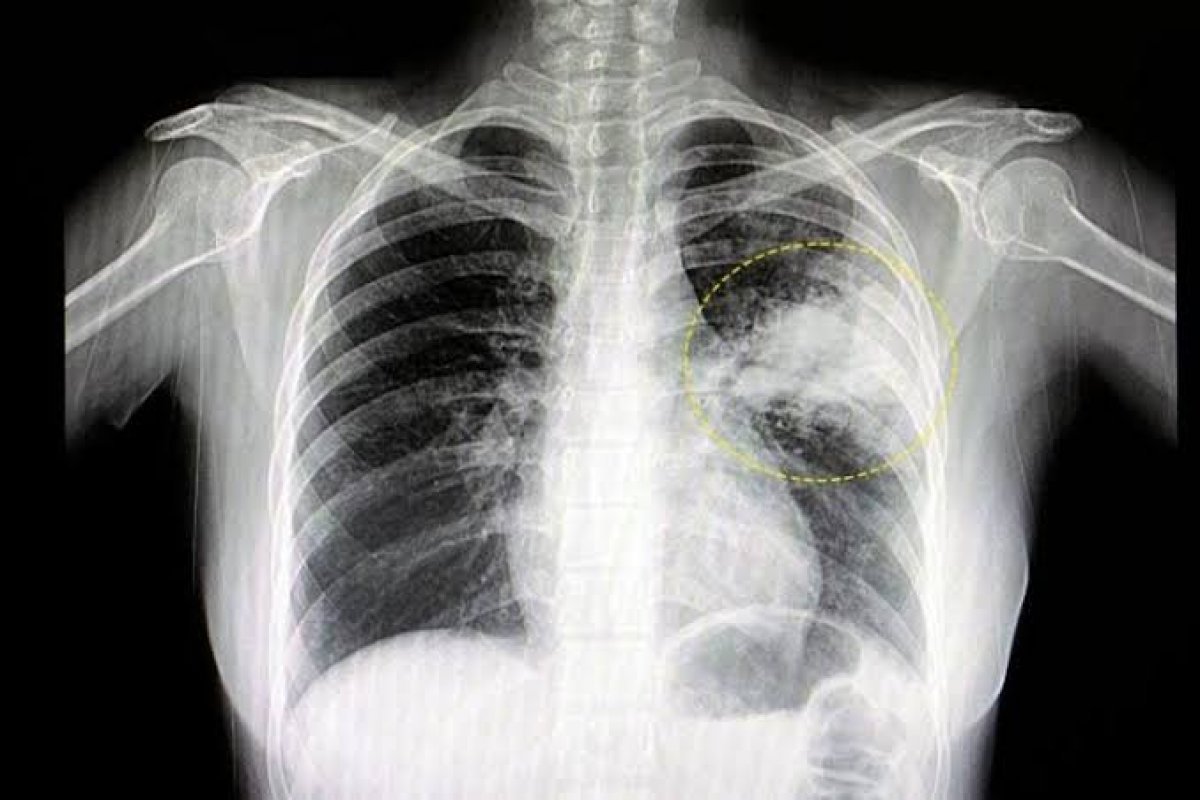

A pneumonia é uma inflamação aguda dos pulmões, que pode ser transmitida pelo ar, saliva, secreções ou transfusão de sangue. A doença pode ser provocada por bactérias, vírus, fungos ou pela inalação de produtos tóxicos. O diagnóstico pode ser difícil, pois geralmente ela apresenta sintomas semelhantes a outras doenças, como tosse, dificuldade em respirar, dor no peito, mal-estar generalizado e febre.